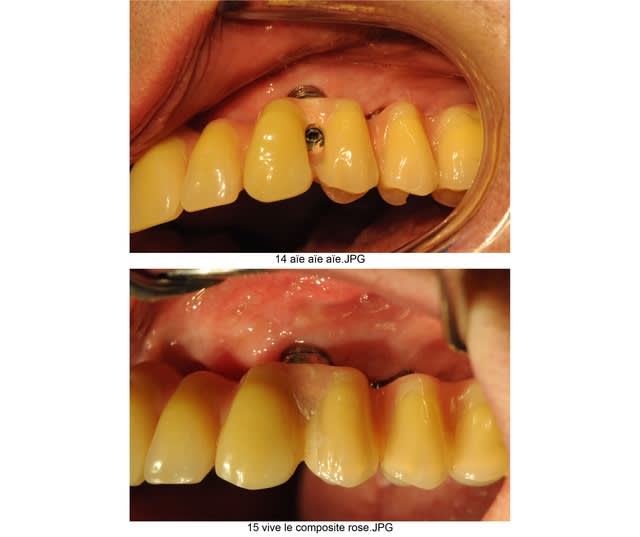

comme on apprends beaucoup de ses erreurs mais aussi un petit peu de celles des autres, je t'envoie justement les photos de mon premier all on 6 .

tu trouvera sans difficultés où j'ai merdé à l'époque.